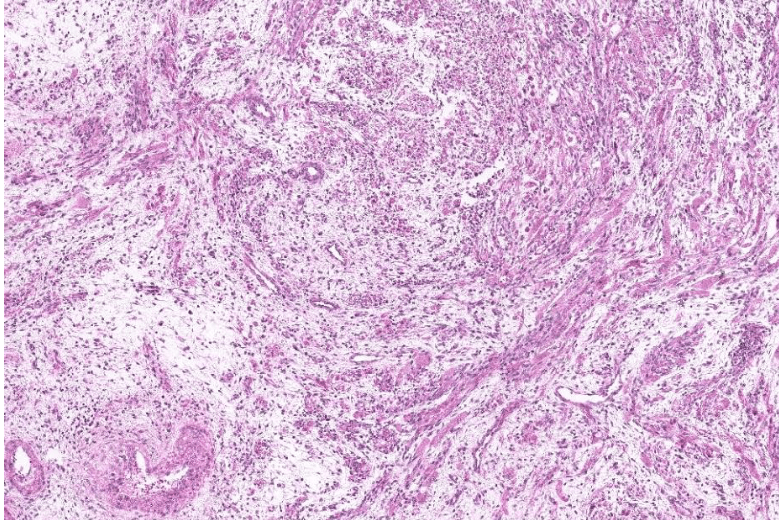

lung adenocarcinoma